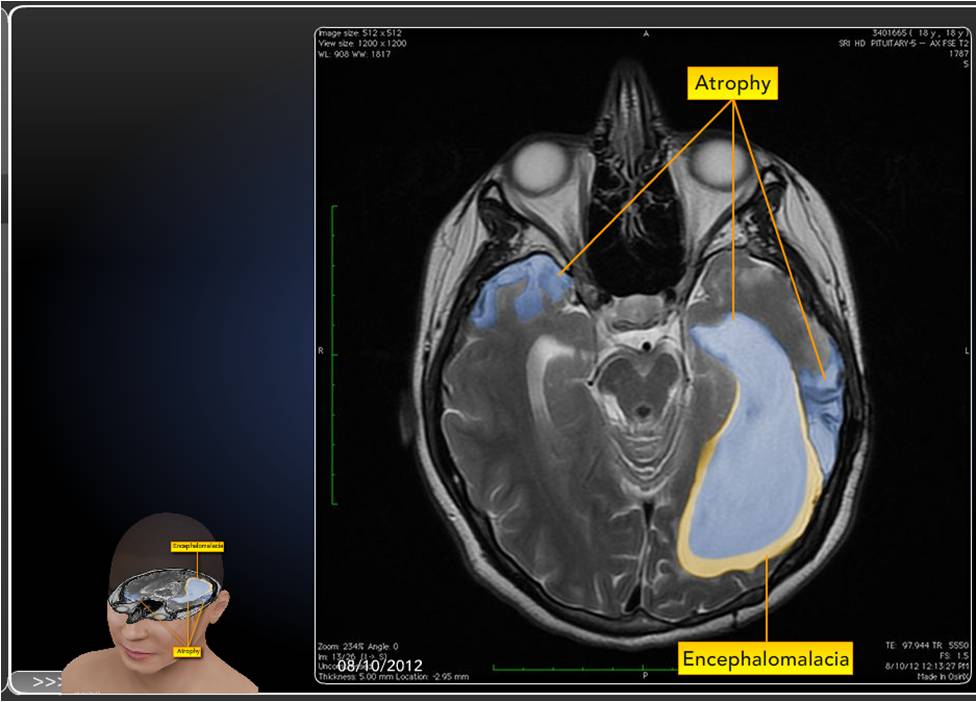

It is that horrible swelling that causes the damage to the left side and front of her brain.

But the doctors say it won’t be easy. Over 1/3 of her brain is dead. They say she now has a 67 IQ. She can’t remember what is said 5 minutes later. She isn’t able to identify an apple if you hold it in front of her and ask her what it is.

And her brain makes things worse, because the damage to her frontal lobe impacts her ability to control her emotions. This causes obsessive compulsiveness, depression, suicidality, and even more hopelessness.

It is that horrible swelling that causes the damage to the left side and front of her brain.

But the doctors say it won’t be easy. Over 1/3 of her brain is dead. They say she now has a 67 IQ. She can’t remember what is said 5 minutes later. She isn’t able to identify an apple if you hold it in front of her and ask her what it is.

And her brain makes things worse, because the damage to her frontal lobe impacts her ability to control her emotions. This causes obsessive compulsiveness, depression, suicidality, and even more hopelessness.